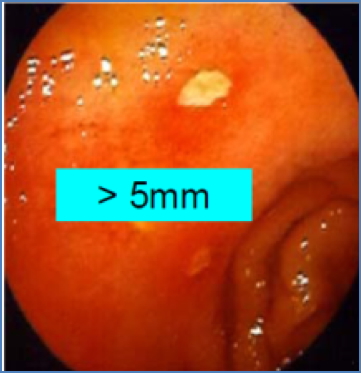

- Typically small, round, single ulcers with sharply punched-out appearance

- Endoscopy + Biopsy – assess ulcer, test for H. pylori, rule out gastric cancer